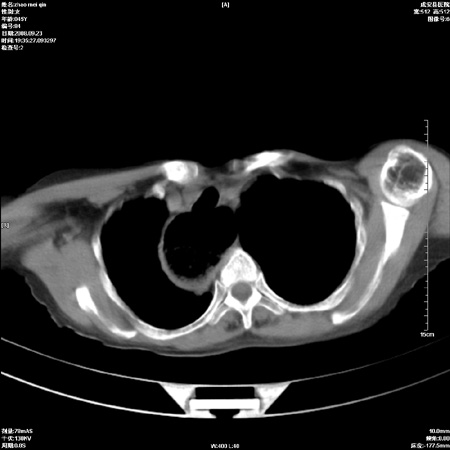

标题: CT15861:女 60 外伤后1小时 胸疼 [打印本页]

标题: CT15861:女 60 外伤后1小时 胸疼

外伤后1小时 胸疼 是外伤后引起的吗?

食道扩张明显下端逐渐变窄,倒像贲门失迟缓

食道ca术后胸腔胃,右肺挫伤?

非外伤性改变,典型的贲门失迟缓症

食道扩张明显下端逐渐变窄,大量食物存留,象贲门失迟缓症。